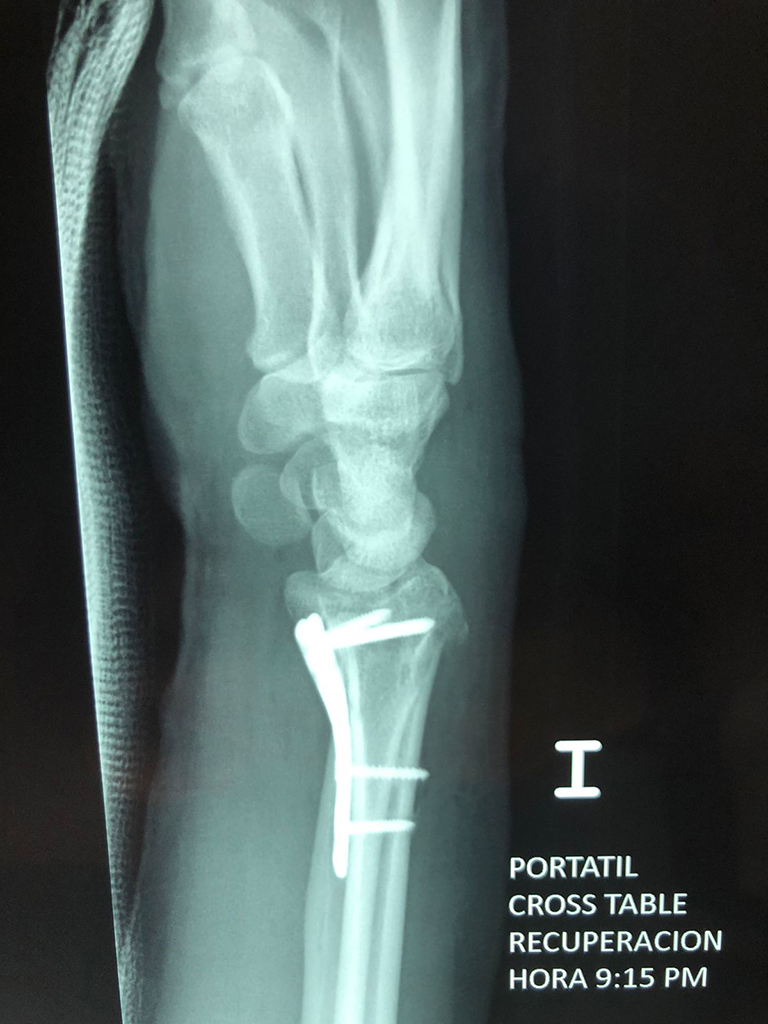

Cirugías de Codos - Cirugías de Muñecas y Manos

Los procedimientos más comunes en cirugía de la mano son aquellos destinados a reparar traumatismos, incluyendo lesiones de tendones, nervios, vasos sanguíneos, y articulaciones; huesos fracturados; y quemaduras, cortes, y otros daños de la piel.